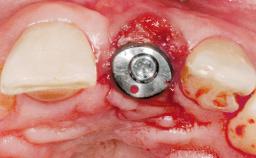

A 30-year-old female patient had lost tooth 21 and was referred to our clinic for consultation and treatment. Due to advanced apical infection, tooth 21 had been extracted two months earlier at another clinic and an acrylic-resin tooth had been bonded to the adjacent teeth. The patient desired implant treatment to avoid any damage to the adjacent natural teeth. While the patient had no history of any systemic disorder, she was a heavy smoker and exhibited medium to advanced periodontitis in the entire jaw. After the initial treatment to achieve a pocket probing depth of less than 4 mm and no bleeding on probing, a decrease in the height of the papillae mesial and distal to the extraction site and overall gingival recession were observed.

Type of Implants One-Piece|Reduced-Diameter

Bone Augmentation Horizontal|Staged

Augmentation Materials Autogenous chips|Membrane

Soft Tissue Grafting Simultaneous

Bone Volume Deficient horizontally, requiring prior grafting